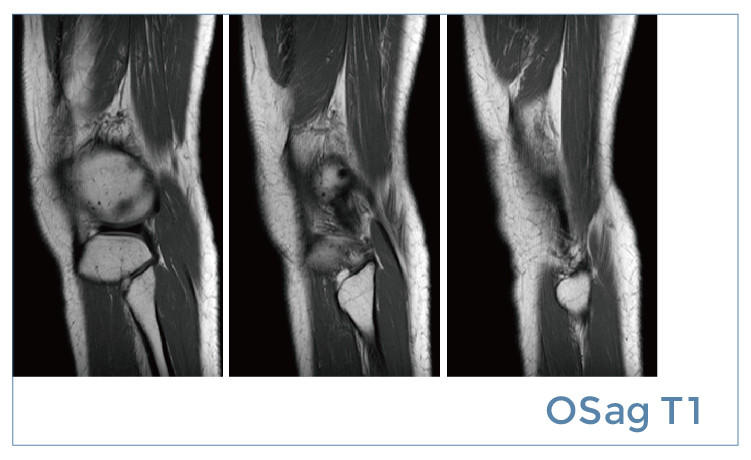

【朗润影像档案】20190510磁共振影像病例结果讨论